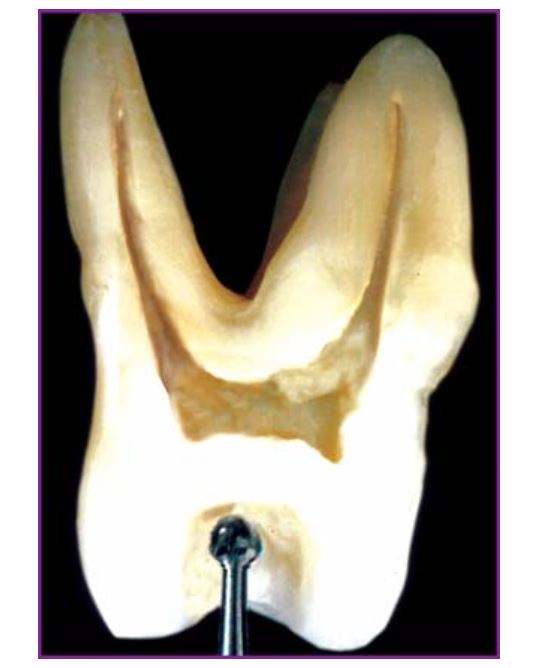

Khi nhìn từ mặt nhai hoặc mặt trong phải thấy rõ tất cả miệng ống tủy (H5.1 a,b).

Răng 6 hàm trên (H5.11).